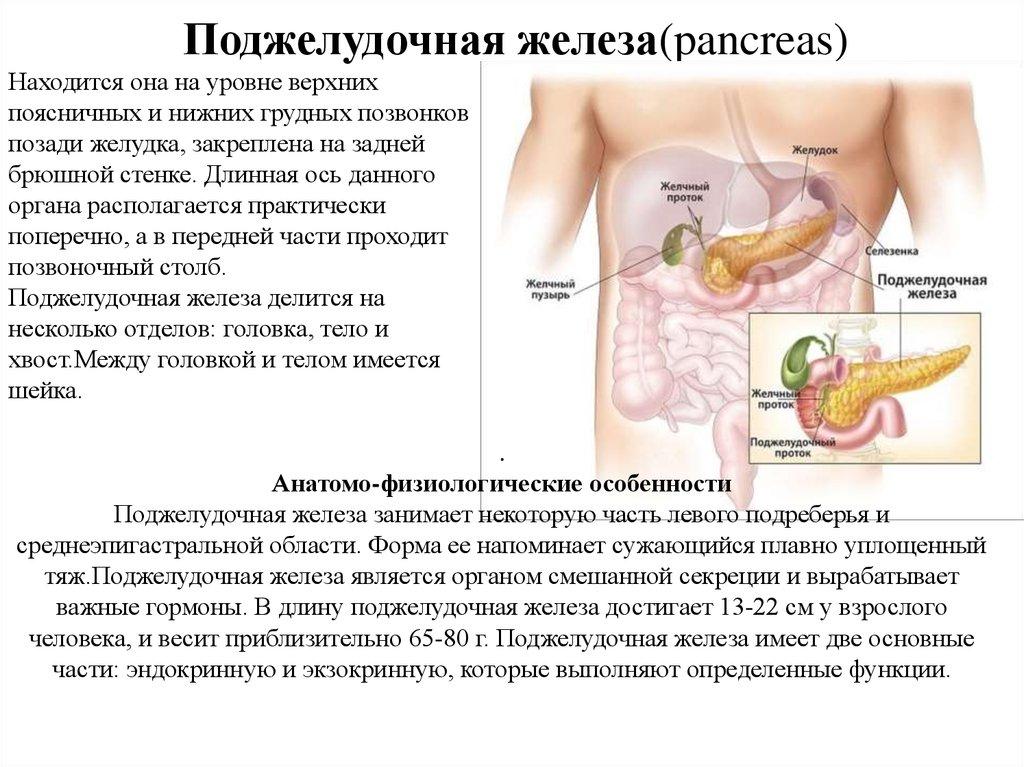

Анатомическое расположение поджелудочной железы

ПЖ располагается в брюшной полости, ближе к I–II позвонкам поясничного отдела позвоночника. Орган плотно крепится на задней стенке желудка, а 12-перстная кишка окружает ее, поддерживая в необходимом положении.

Параметры ПЖ взрослого человека в норме должны быть 20-25 см, вес – 70-80 граммов.

По анатомическому строению орган делится на 3 составных части: это головка, тело и хвост. Головкой ПЖ обращена к желчному протоку, тело находится за желудком, ближе к его нижней части. Рядом с телом в норме располагается поперечно-ободочная кишка. Хвостом ПЖ обращена к селезенке, и уходит к левому подреберью. По отношению к пупку, со стороны брюшной стенки, ПЖ расположена над ним, на 5-10 см выше.